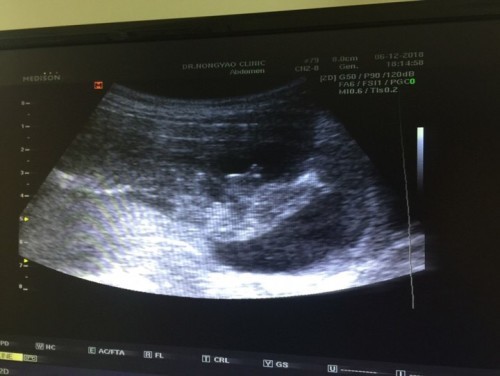

?ตอนนั้นผมได้พาแฟนไปซาวเพศที่คลีนิคช่วง3เดือนครึ่ง หมอบอกว่าได้ลูกชาย80% ตอนนี้อายุครรภ์ได้34สัปดาห์ ไม่ทราบว่า เพศของลูกสามารถเปลี่ยนได้ไหมคับ เพราะตอนที่ไปซาวอายุครรภ์ยังน้อย ?? รูปซาวผมก็ดูไม่เป็น